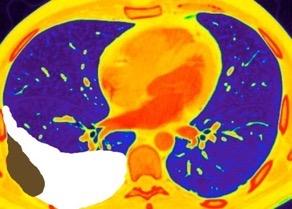

En el hemotórax, los elementos formes de la sangre tienden a depositarse en la parte más declive

Polireddy K et al. Blunt thoracic trauma: role of chest radiography and comparison with CT findings and literature review . Emerg Radiol 2022.